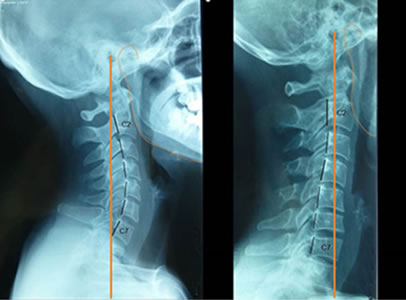

Rectificación Cervical

En RPG decimos que este tipo de morfología es un desequilibrio muscular anterior, ya

que la principal musculatura y tejido conectivo responsable de esta retracción se

sitúa por delante de la línea de gravedad (la línea naranja que podemos observar en

la imagen )